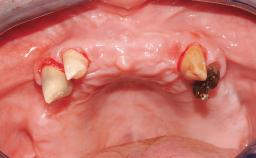

Transition from an “irrational to treat” Maxillary Dentition to a Full-Arch Segmented FDP by Early Loading of Eight Implants Placed Using the Staged Approach

The staged approach permits the transition from an “irrational to treat”dentition to a full arch implant supported restoration without any need to use a removable provisional prosthesis or to apply the immediate-placement and immediate-loading techniques.  A failing dentition is the usual indication for a staged treatment. On the other hand, the dentition should still contain many residual teeth, but with few or none of them being suitable for use as definitive abutments for a full-arch fixed restoration.This situation is usually the result of advanced periodontal disease or of the failure of an extensive fixed prosthesis.

Case Type Edentulous Maxilla

Infection at Implant Site None Chronic Acute